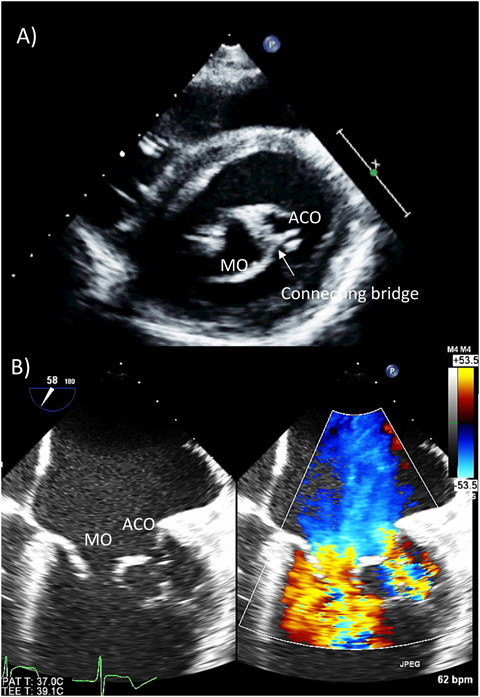

B) 重複僧帽弁口(double-orifice mitral valve: DOMV)(Fig. 6)

僧帽弁口が弁の過剰組織により複数の開口部に分離されるものを指し,通常それぞれの弁下に独立した弁下組織が形成される(Fig. 6B11).独立した弁下組織があることで,二次的な弁の穿孔と鑑別される12).大部分の症例において他の先天性心疾患に合併して存在し,房室中隔欠損に合併するものが約半数を占め,他には大動脈弁二尖弁や大動脈縮窄等に合併することが多い.約半数で閉鎖不全を呈するが,約1/3は正常の弁機能を有し,重度の狭窄を呈するものは約1割程度である.

Pediatric Cardiology and Cardiac Surgery 33(2): 140-156 (2017)

Fig. 6 Double orifice mitral valve

(A) Transthoracic short axis view of a double orifice of the mitral valve. There are two distinct orifices of the mitral valve. (B) Transesophageal echocardiography with color Doppler. Note the separate inflows in the mitral valve and the two distinct pairs of chordae supporting each orifice. ACO: accessory orifice; LVOT: left ventricular outflow tract; MO: main orifice.